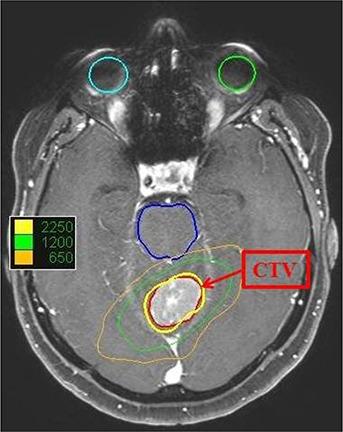

Prolonged treatment execution time is a concern in CyberKnife robotic radiosurgery. Beam reduction and node reduction technique, and monitor unit optimization methods are adopted to reduce the treatment time. Usage of single collimator in the CyberKnife treatment plan can potentially reduce collimator exchange time. An optimal single collimator, which yields an acceptable dose distribution along with minimum number of nodes, beams, and monitor units, can be a versatile alternative for shortening treatment time. The aim of the present study is to find the optimal single collimator in CyberKnife treatment planning to shorten the treatment time with the acceptable dose distribution. A spherical planning target volume PTV1 was drawn in an anthropomorphic head and neck phantom. Plans with same treatment goals were generated for all the 12 collimators independently. D(95%) was selected as the prescribing isodose and the prescribed dose was 10 Gy. The plan of the optimal collimator size was evaluated for conformity, homogeneity, and dose spillage outside the target. The optimum collimator size and the target dimensions were correlated. The study was repeated with two other target volumes PTV2 and PTV3 for generalizing the results. Collimator sizes just above the diameter of the spherical PTVs were yielding least number of nodes and beams with acceptable dose distributions. The collimator size of 35 mm is optimum for the PTV1, whose diameter is 31.4 mm. Similarly, 50 mm collimator is optimum for PTV2 (diameter= 45.2 mm) and 20 mm collimator is optimum for PTV3 (Diameter = 17.3 mm). The total number of monitor units is found to reduce with increasing collimator size. Optimal single collimator is found to be useful for shortening the treatment time in spherical targets. Studies on two clinical targets, (a brain metastasis and a liver metastasis cases) show comparable results with the phantom study.

在 CyberKnife 机器人放射外科中,治疗执行时间延长是一个关注点。可以采用减少射束和节点数量以及优化监测单位的方法来缩短治疗时间。在 CyberKnife 治疗计划中使用单个准直器可以潜在地减少准直器更换时间。一个最佳的单准直器,可以产生可接受的剂量分布,同时具有最小数量的节点、射束和监测单位,是缩短治疗时间的多功能替代方案。本研究的目的是在 CyberKnife 治疗计划中找到最佳的单准直器,以在可接受的剂量分布下缩短治疗时间。在人体头颈部模型中绘制了一个球形计划靶区(PTV1)。为每个 12 个准直器独立生成具有相同治疗目标的计划。选择 D(95%)作为规定等剂量线,规定剂量为 10 Gy。评估了最佳准直器尺寸的计划的适形性、均匀性和靶区外剂量泄漏。对目标尺寸和最佳准直器尺寸进行了相关性分析。对另外两个靶区 PTV2 和 PTV3 进行了研究,以推广结果。直径略大于球形 PTV 直径的准直器可产生具有可接受剂量分布的最少节点和射束数量。对于 PTV1(直径为 31.4mm),35mm 的准直器是最佳的;对于 PTV2(直径为 45.2mm),50mm 的准直器是最佳的;对于 PTV3(直径为 17.3mm),20mm 的准直器是最佳的。随着准直器尺寸的增加,监测单位的总数减少。研究表明,对于球形靶区,最佳的单准直器可用于缩短治疗时间。对两个临床靶区(脑转移和肝转移病例)的研究结果与模型研究相似。